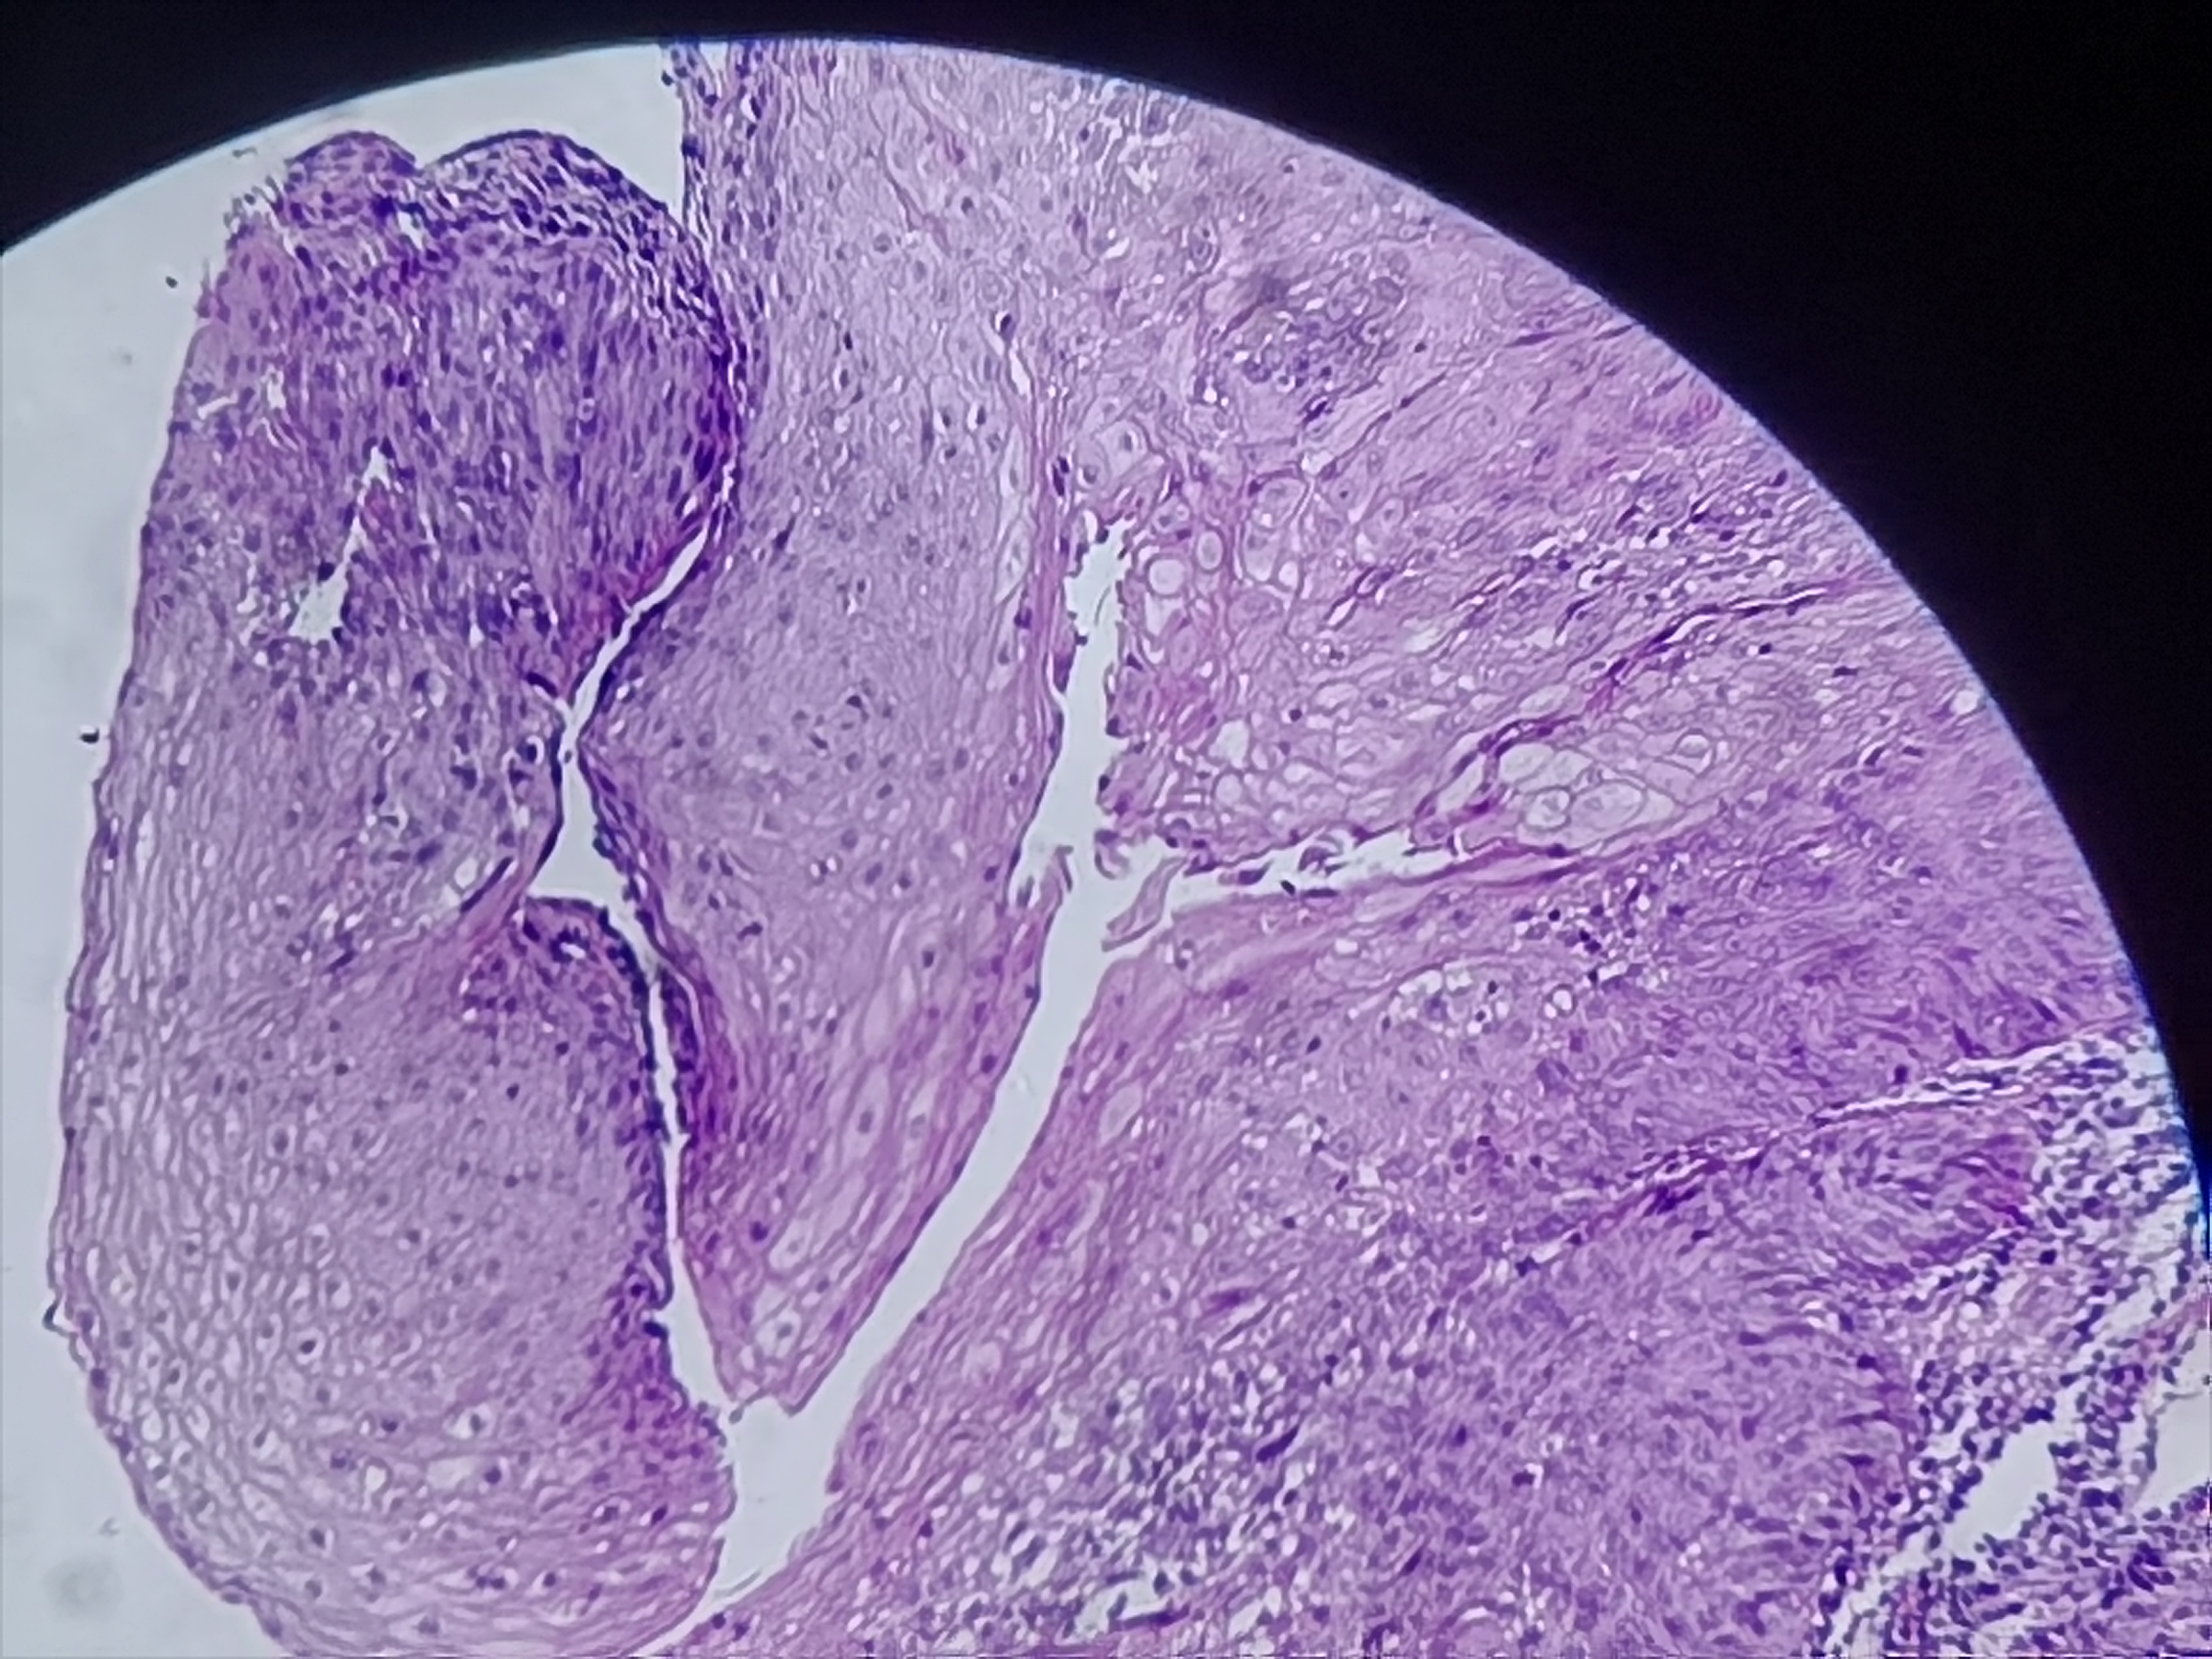

食管活检

男

61岁

食管癌

食管距门齿20cm处可见不规则病灶,质脆,易出血,管腔狭窄,镜子不能通过

食管粘膜活检

灰白色组织3块

考虑符合:鳞癌